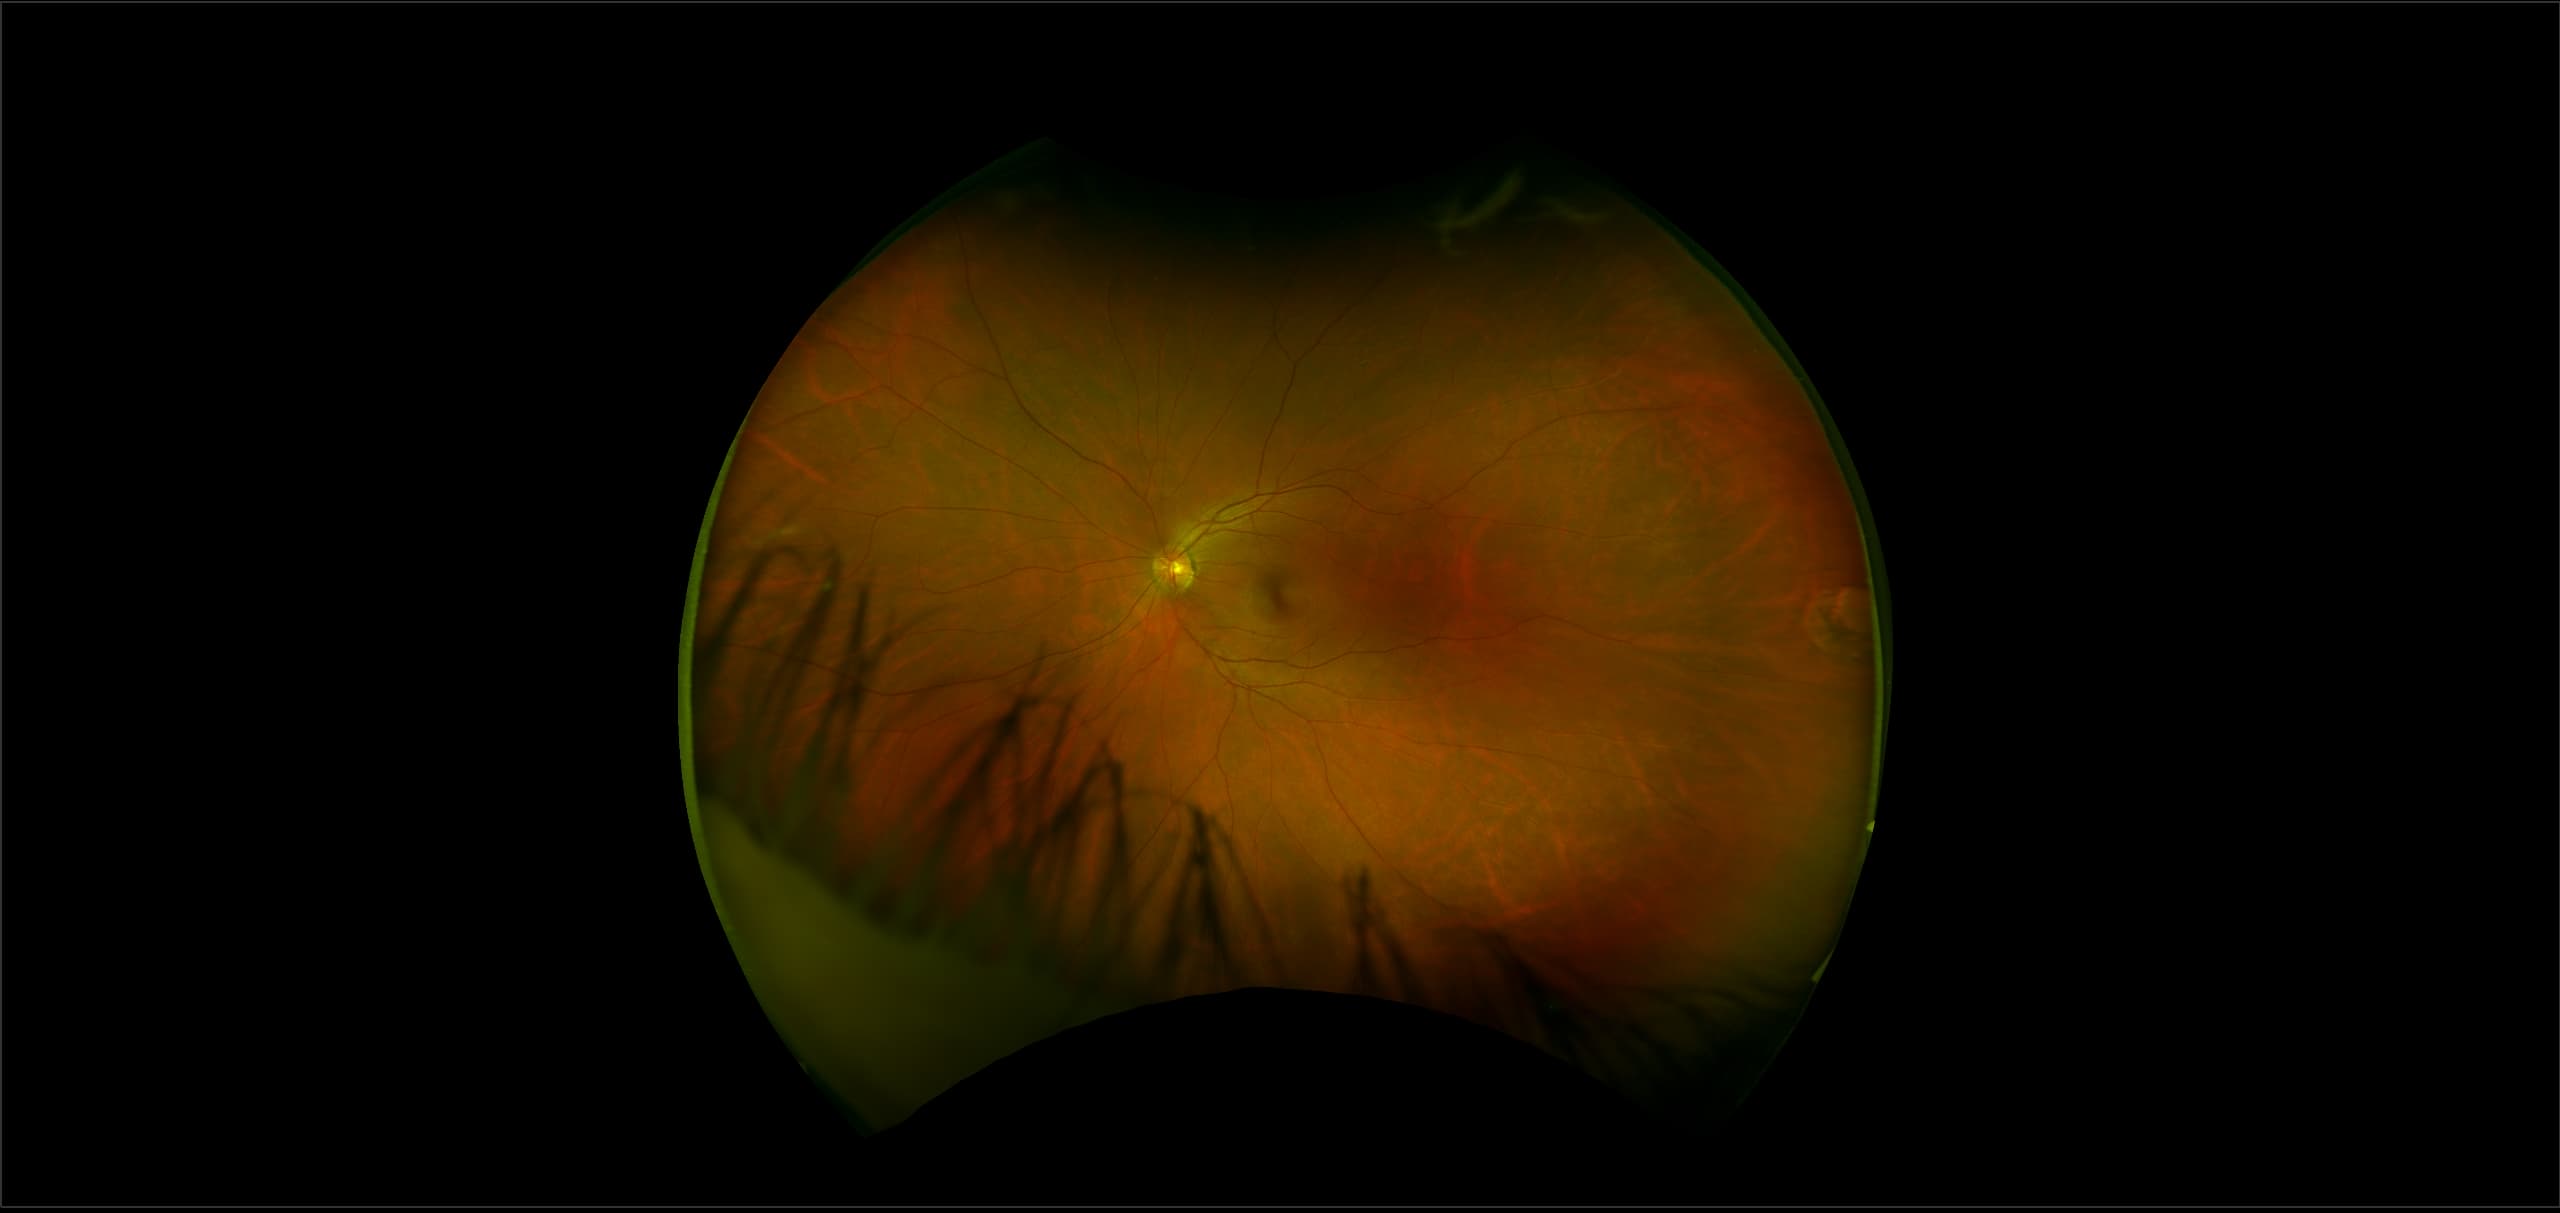

MonacoPro - Peripheral Atrophy, RG

Retinal atrophy occurs when there is damage to the tissue in the retina that causes partial or total deterioration of your vision.